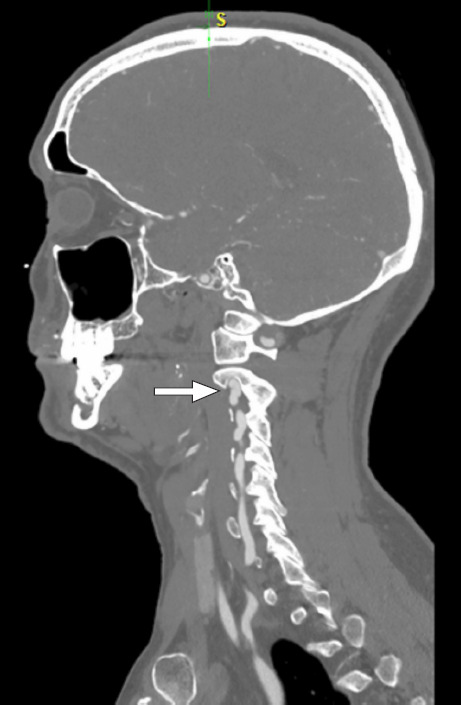

A male patient presented with cardiac arrest attributed to anterior ST-segment elevation myocardial infarction from type 1 spontaneous coronary artery dissection. Subsequent imaging confirmed fibromuscular dysplasia in noncoronary arterial segments. The patient was started on guideline-directed medical therapy and referred to cardiac rehabilitation, showing substantial improvements in clinical status. With greater awareness and advancements in imaging, spontaneous coronary artery dissection has been more frequently recognized, and although as many as 81% to 92% of all cases occur in female patients, it can be seen among men, as well. Adjunctive imaging for arteriopathies may help establish the diagnosis for equivocal causes of acute coronary syndrome in women and men.

Abstract Image